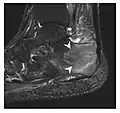

Figure 9: Proximal metaphyseal fatigue fracture of the tibia in a 27-year-old recent male military recruit. (a) Anteroposterior radiograph is within normal limits. (b) Coronal T1-weighted MR image shows a marked linear hypoattenuation along the medial tibial metaphysis (arrow) surrounded by diffuse hypointensity in keeping with posttraumatic edema.[1]

a

b